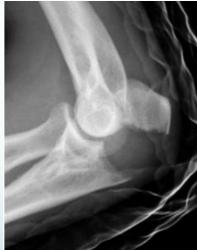

Tension-band Wires

- Indications:

- Patellar and olecranon fractures

- Possible to use in malleolar fractures

- Application:

- K-wires applied first, then tension-band wire